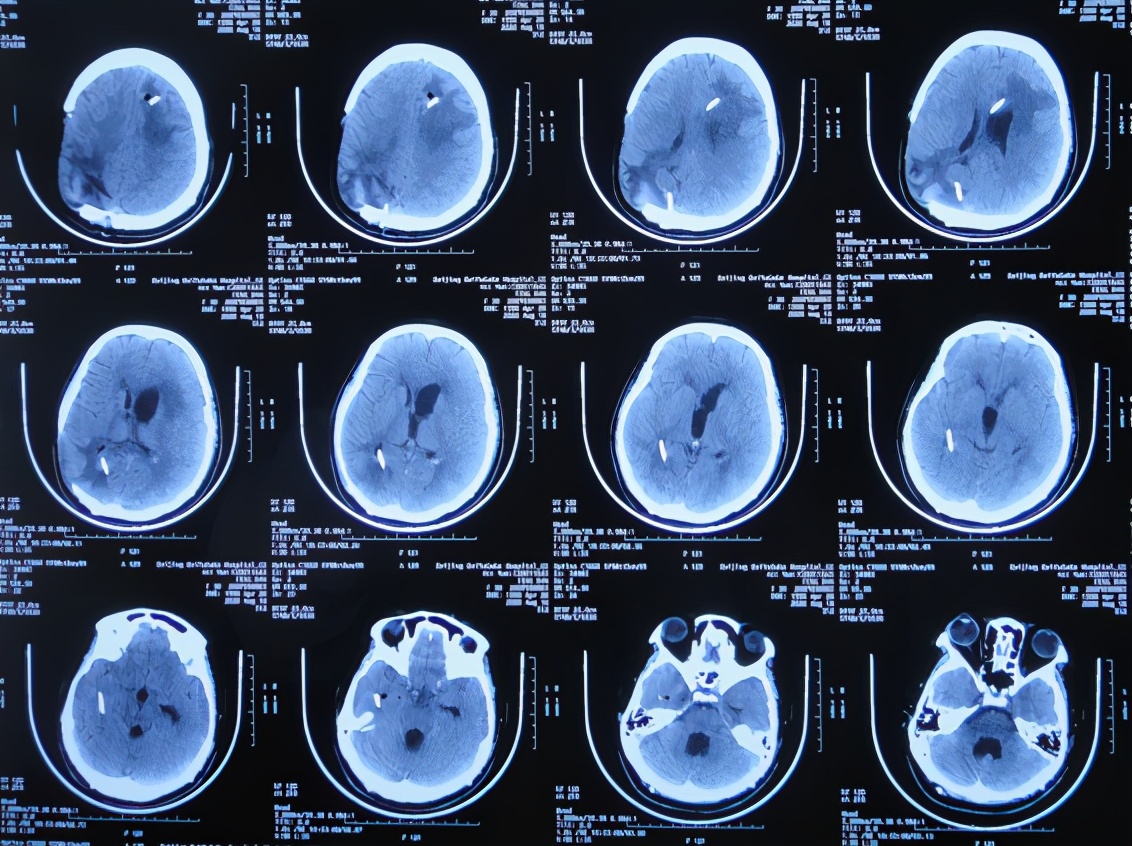

开颅术后26天2020年4月28日(腰大池引流管第4次脱出后5天),复查头颅CT发现幕上脑室系统扩张( 图-5 );但因患者症状好转,可在搀扶下独立行走,未予处理。

图-5: 2020年4月28日头颅CT